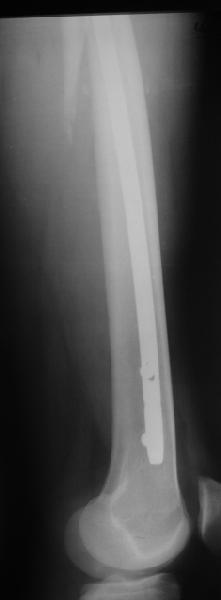

Да, сейчас это и у нас самый напрашивающийся выбор. Сделали гвоздем ChM, картинки в приложении.

У молодых реконструкционный гвоздь самое то. При остеопорозе надо что-то помассивнее.